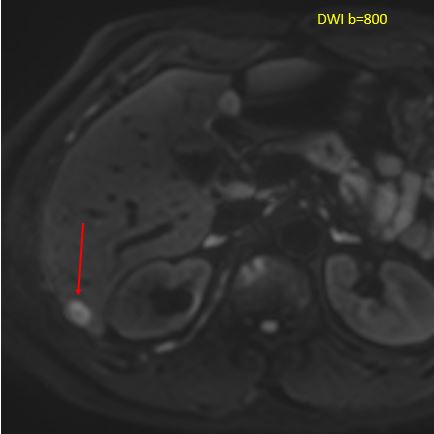

MRI with DWI showing lesion.